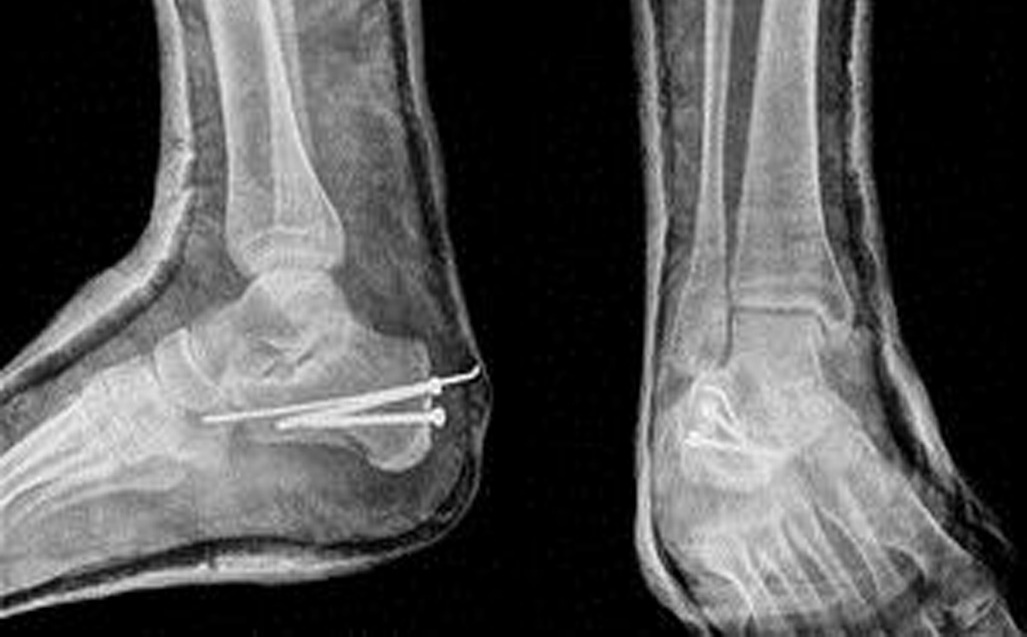

The company Synthes Costa Rica S.C.R. Ltda provides elastic titanium nails and osteosynthesis systems to 24 hospitals in this Central American country through a contract with the Caja Costarricense de Seguro Social (CCSS). The company’s current contract will finish in September and many were surprised to hear that it was recently renewed despite a fraud investigation.

Reports confirm that the CCSS will continue to purchase nails from this company until April 4th, 2015 under one contract worth $57,600 and the osteosynthesis systems until June 15th, 2015 under a second contract for $448.500.